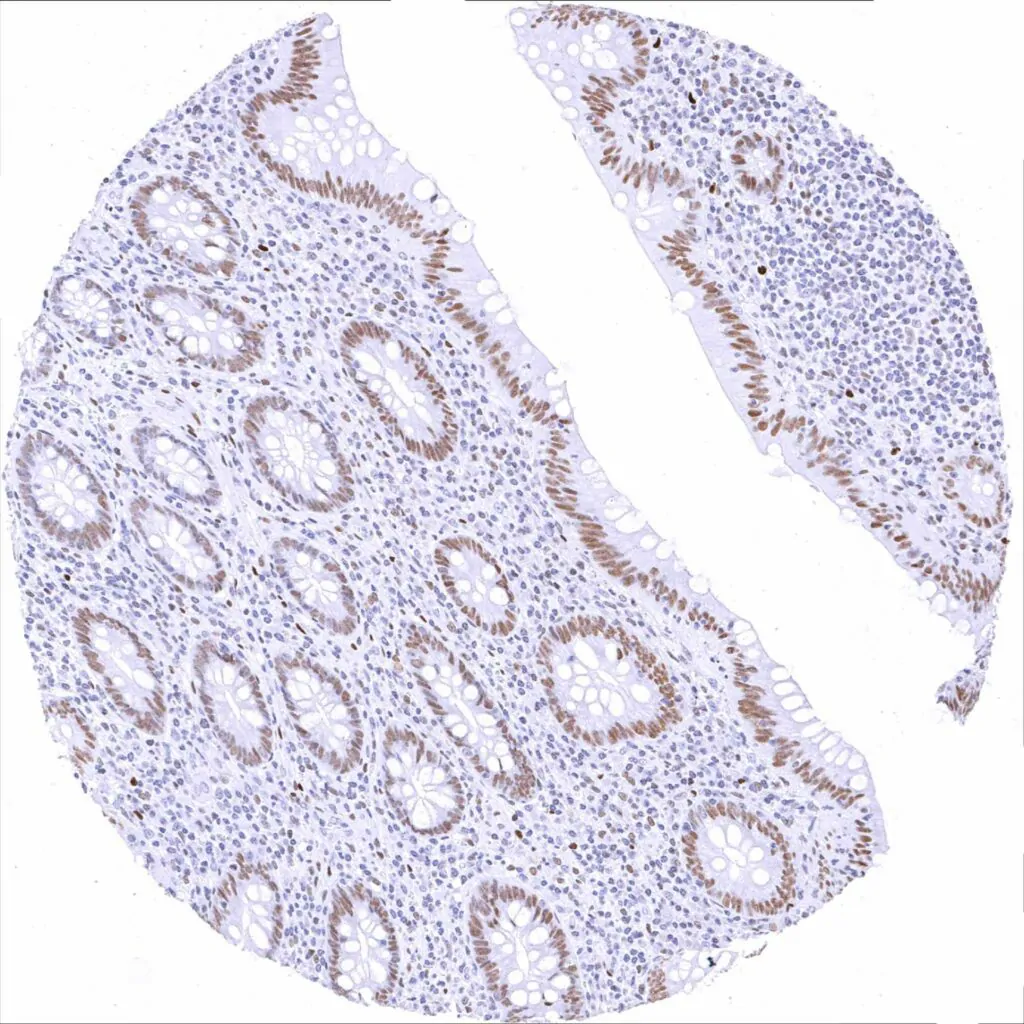

Rectum, mucosa – Weak to moderate TLE1 staining in epithelial cells. Staining is stronger in crypts than at the surface